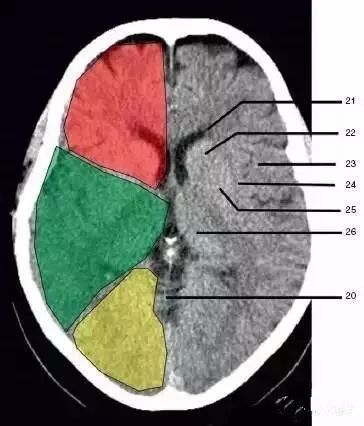

20、小脑上池(Third ventricle)

21、侧脑室前角 (Frontal horn of lateral ventricle)

21a、第三脑室 (Third ventricle):绿色部分为颞叶(Temporal Lobe),浅红色部分为额叶(Frontal Lobe),黄色部分为枕叶(Occipital Lobe)

22、尾状核头部(Head of caudate nucleus)

23、岛叶(Insular cortex)

24、外囊(External capsule)

25、豆状核(Lentiform nucleus)

26、丘脑(Thalamus) :绿色部分为颞叶(Temporal Lobe),浅红色部分为额叶(Frontal Lobe),黄色部分为枕叶(Occipital Lobe)